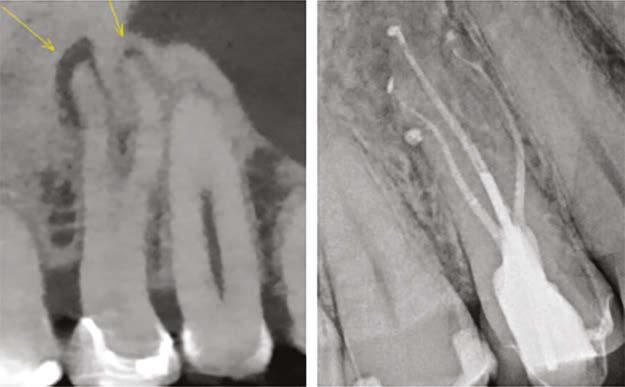

1: 3D print in clear acrylic of maxillary central incisor with mid-root lateral canal and apical canal bifurcation. Note the calcified pulp chamber

accurate prediction because in 2017, after printing resolution got down to 0.016 mm, I was able to print the first extracted tooth replicas in both clear and opaque inks.

Since then, TrueTooth and TrueJaw replicas have been used worldwide, and of course, in my training lab in Santa Barbara. Here are a couple of things I’ve learned in the 8 years since their advent:

Figure

a replica, they will never ledge a human root canal again for the rest of their careers.

4. Clear and opaque replicas are ideal for teaching mental imaging skills. Mental imaging is the most important skill a dentist brings to a root canal party, and while some of us have a natural ability in that regard, most of us need help figuring out how to do that. Training in clear replicas provides a view of exactly what is happening; for instance, when a rotary file is cutting through a curved canal, The best experience is to first do it in a clear replica and see it, then do the same procedure without directly seeing it in an opaque replica. Lots of “aha’s” happen with this teaching method. The results have been amazing (Figures 2-6).